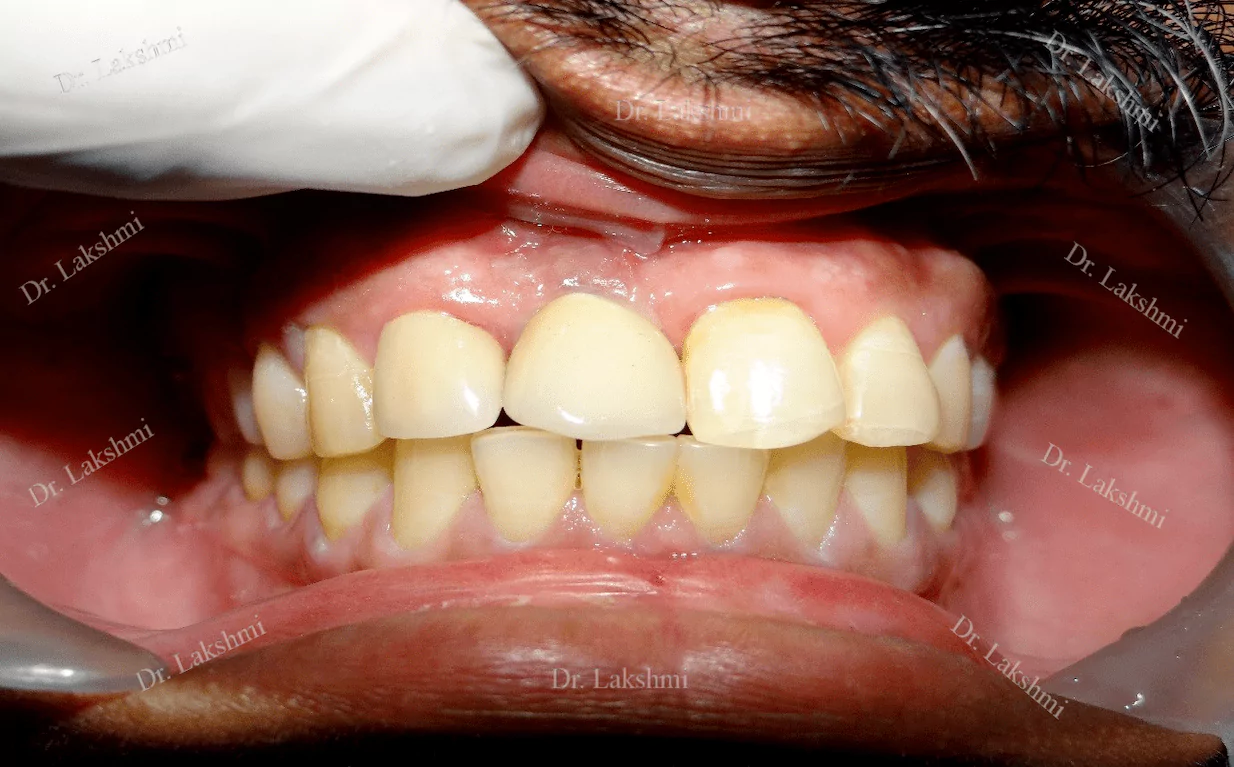

Dental implants have come to define modern dentistry in the last few decades. Dental implants are cemented to the jawbone and an abutment is used as a support for the dental crown that is placed over it. There are a single piece, two-piece and three-piece abutments available for implants. Titanium fuses naturally with the jawbone and that makes it a perfect fit as an implant. There are several dental implant techniques available to opt from, for a patient. The freedom to opt also depends on the condition of the jawbone and the gum.

Replacement of All Teeth: Replacement of all teeth can be done either by the placement of implant supported dentures or by the placement of multiple unit bridges placed over implants.